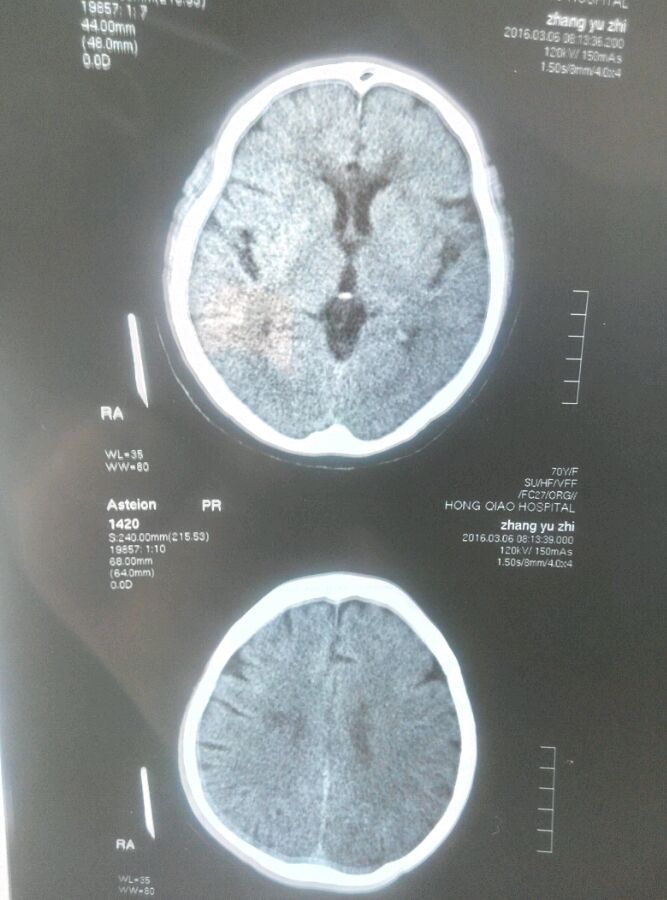

请朋友们帮忙看看我的CT片,什么状况?谢谢啦

腔隙性脑梗塞

两侧基底节隙裂性脑梗死

这个拍的好,双侧腔隙性脑梗塞。

多大腔隙性脑梗塞,右侧基底节区软化灶形成